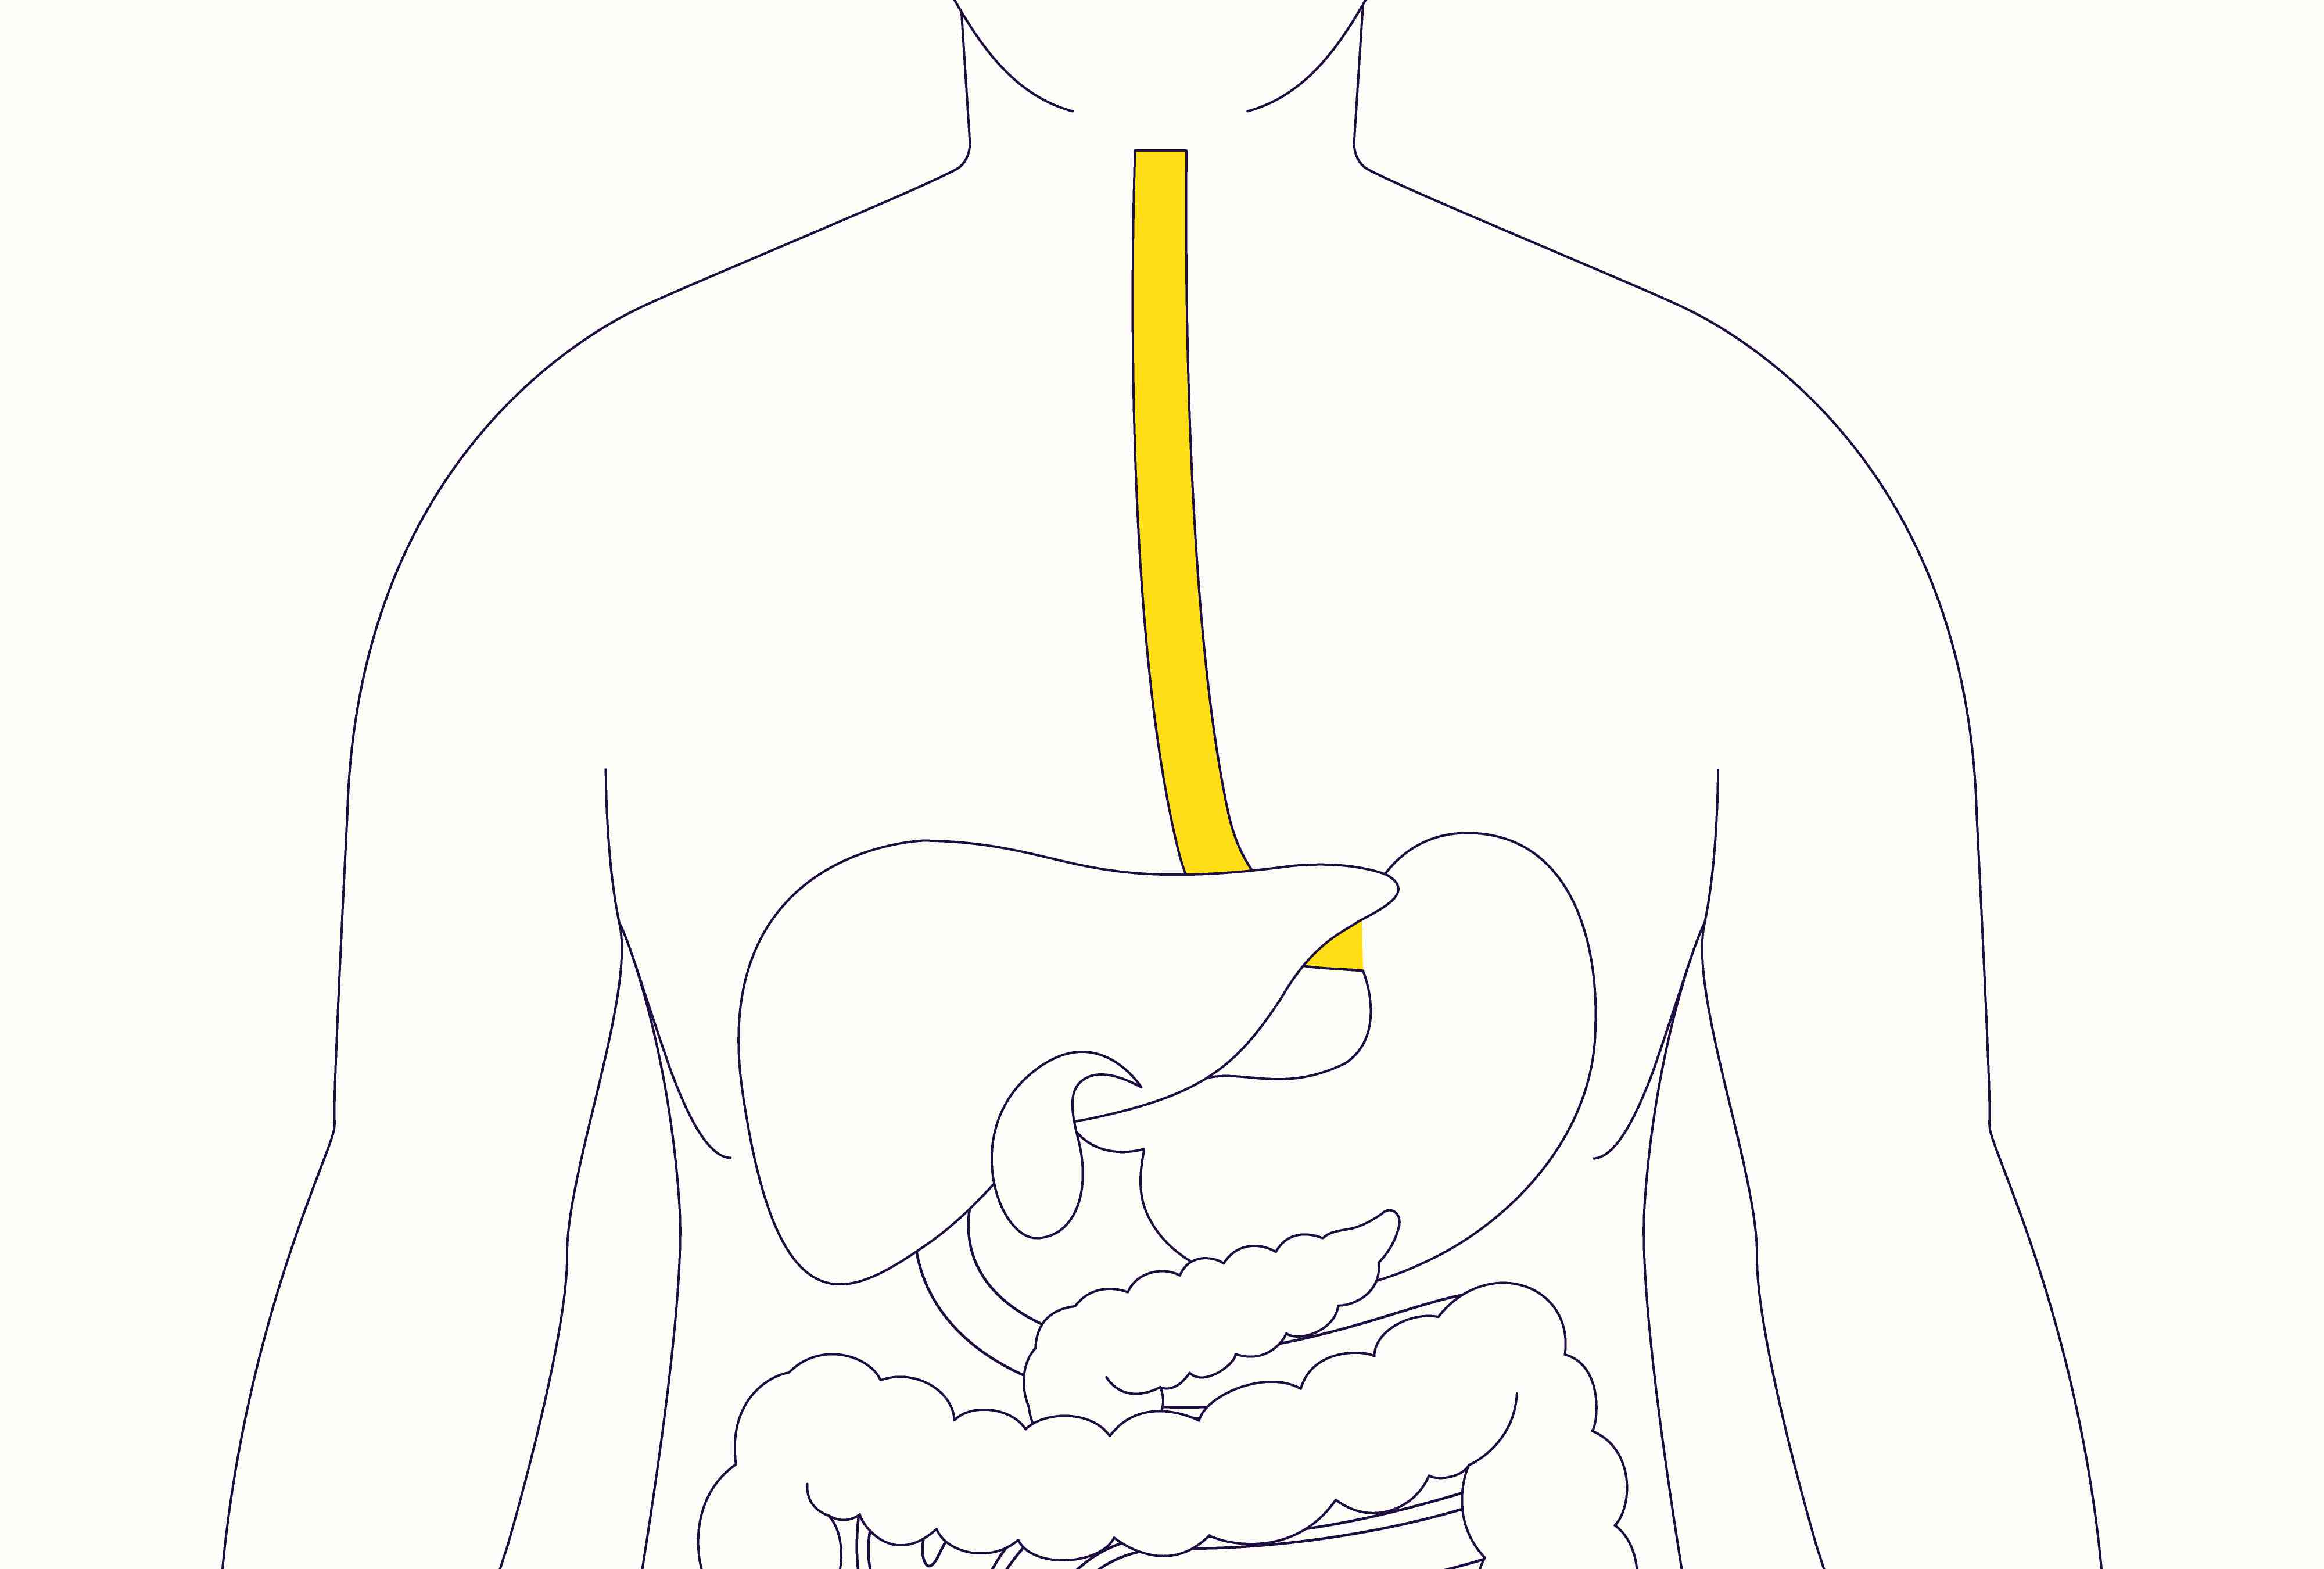

Esophagus

Diaphragm

Liver